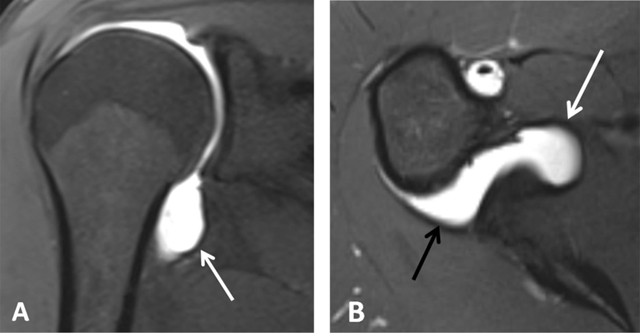

Figure 4

Normal humeral head versus Hill-Sachs lesion. (A) On the axial T2 gradient echo weighted MR image, there is a slight flattening of the posteroinferior surface of the humeral head (arrow), which is a normal finding. (B) Axial fat saturated T2-weighted MR image obtained at the level of the coracoid process (arrowhead, B) typically shows a Hill-Sachs defect (arrow) in a patient with history of anterior shoulder dislocation.